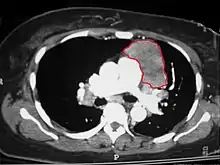

CT scan of the chest revealing a large necrotic mass in the left anterior mediastinum (indicated by the red line). Histology later established the diagnosis of a thymoma.

When a thymoma is suspected, a CT/CAT scan is generally performed to estimate the size and extent of the tumor, and the lesion is sampled with a CT-guided needle biopsy. Increased vascular enhancement on CT scans can be indicative of malignancy, as can be pleural deposits.[1] Limited biopsies are associated with a very small risk of pneumomediastinum or mediastinitis and an even-lower risk of damaging the heart or large blood vessels. Sometimes thymoma metastasize for instance to the abdomen.[5]